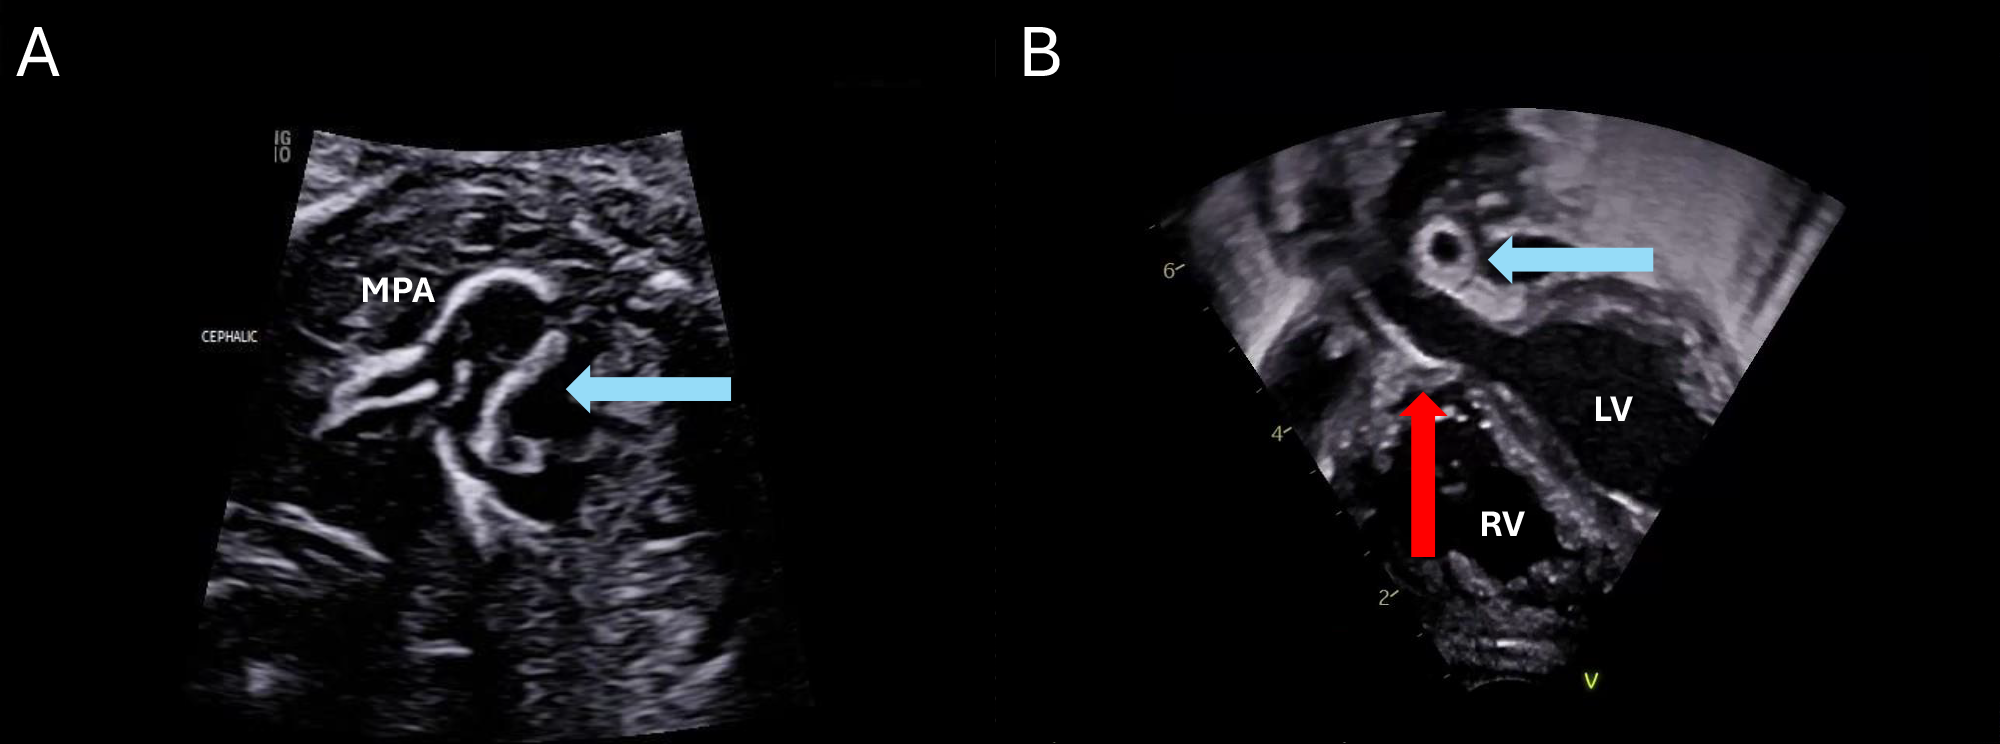

GACI can present in utero with polyhydramnios, nonimmune hydrops, and echobright atrioventricular valves, aorta, and pulmonary arteries due to fibrous intimal thickening and calcification.2,4 Postnatally, it can result in respiratory failure, pulmonary hypertension, myocardial ischemia, hepatic and kidney ischemic injury, and ischemic neurologic injury. Typical features on postnatal echocardiography include echobright walls of the aorta and pulmonary arteries. The presence of calcifications can be confirmed with a noncontrast computed tomography (Figure 2).

Figure 2: Noncontrast Computed Tomogram Confirming Presence of Calcifications

Coronal oblique image from noncontrast computed tomography of the abdomen and pelvis showing calcification of the abdominal descending aorta (red arrow) and common iliac arteries (blue arrows).